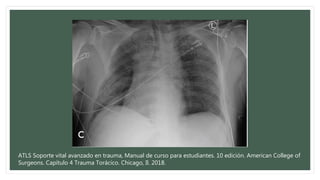

Neumotórax simple

• Consecuencia de la entrada de aire al

espacio virtual entre la pleura visceral y

parietal.

• La laceración del pulmón con fuga de aire es la causa más común.

• Realizar un examen físico exhaustivo del tórax

• Se observan los movimientos de la pared torácica y se comparan.

• Los ruidos respiratorios está habitualmente disminuidos en el lado afectado.

• A la percusión hiperresonancia.

• Rx simple de tórax

• Tx: Tubo de tórax en el quinto espacio intercostal justo por delante de la línea axilar media.

Vigilancias sólo por cirujano con experiencia.